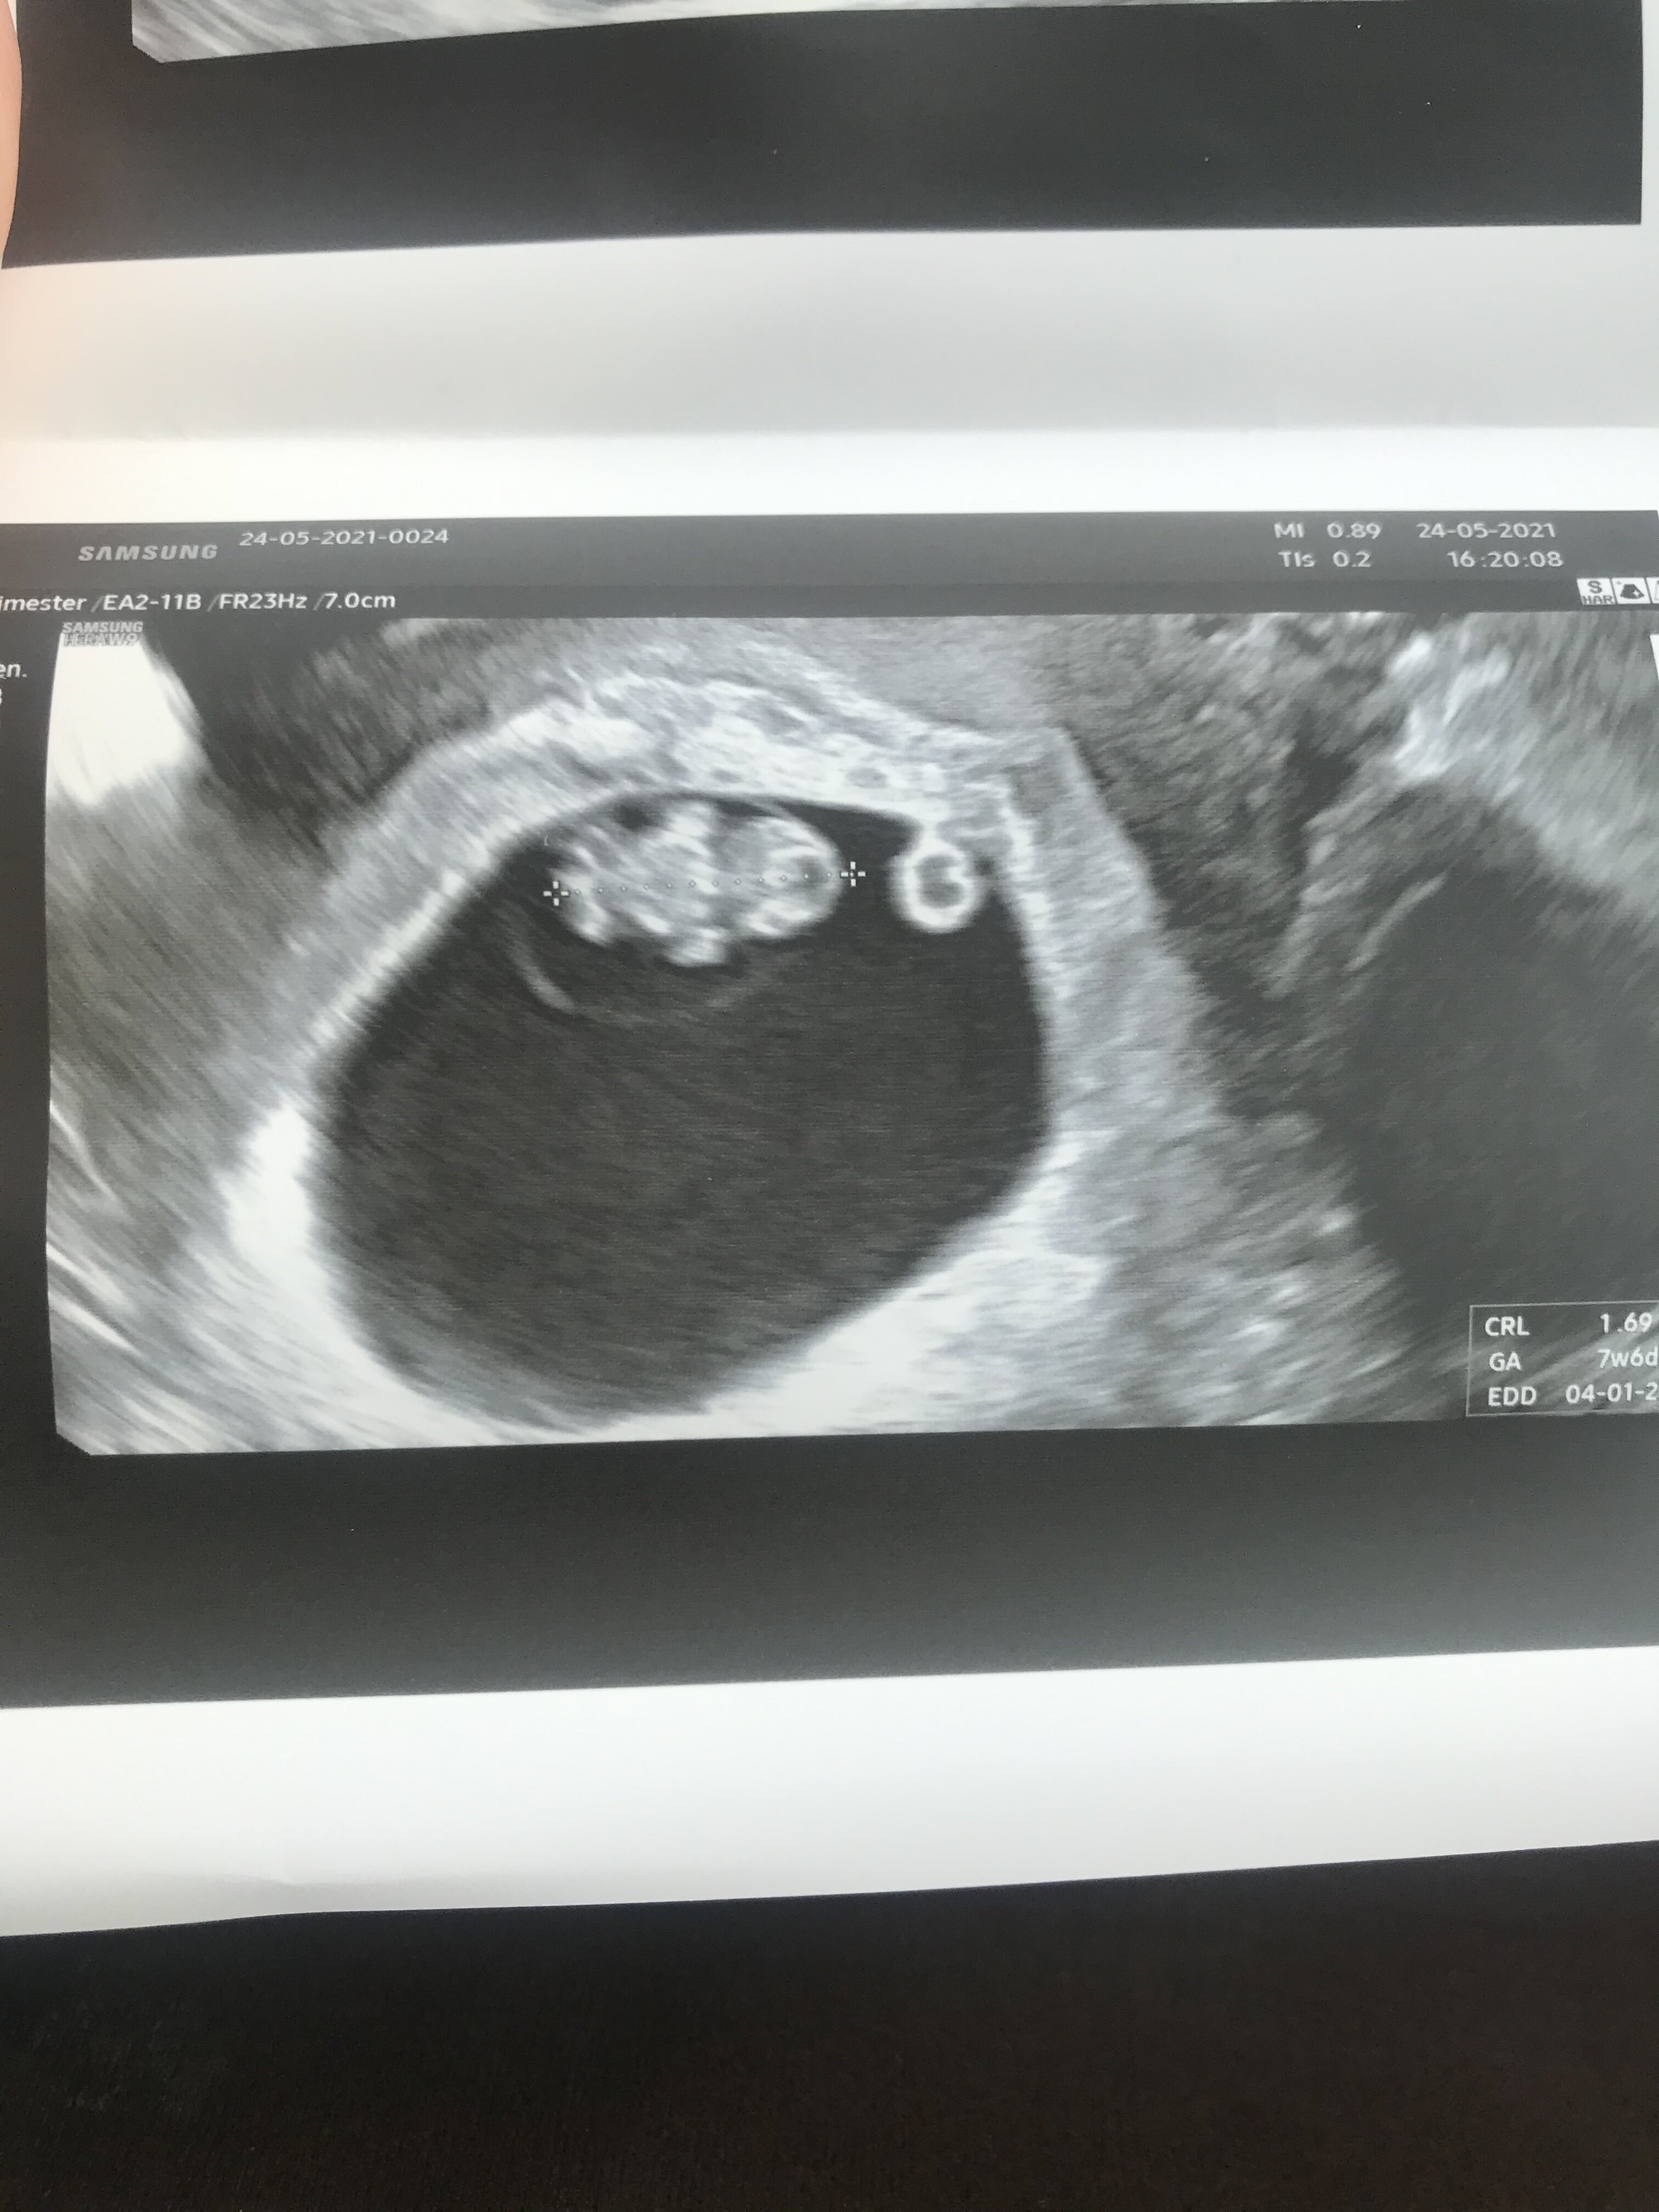

Dziewczyny, melduje się po wizycie 😊 dzidzia ładnie rośnie, zamiast 8+3 okazało się, ze jest 8+4 wiec idealnie :) serduszko bije 164 uderzenia na minutę, następna wizyta dopiero za 4 tygodnie, wtedy tez będzie usg prenatalne, muszę jakoś wytrzymać :D

Załączniki

• 4880290A-C9D2-4983-98DB-4755A8D2ADE1.jpeg

4880290A-C9D2-4983-98DB-4755A8D2ADE1.jpeg

447,4 KB · Wyświetleń: 130